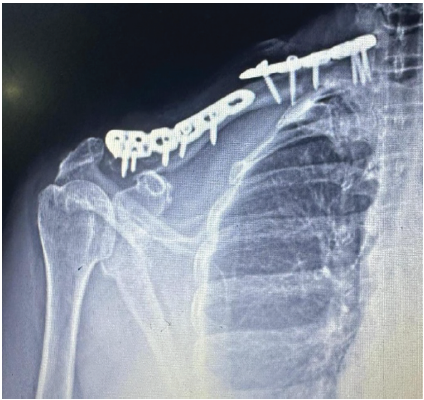

To avoid stress raisers, plates were fixed at different planes. Early mobilization was initiated post-operatively. Arm abduction was restricted to <90°. For 12 weeks, weight-bearing activities were avoided. Weekly follow-up was advised for the initial 6 weeks, followed by 3 weeks of follow-up till 3 months, subsequently at 6 months interval [fig-6/7]. The 6-week post-operative X-ray showed signs of fracture healing and a maintained anatomical reduction. The 1-year follow -up X-ray showed a united fracture. Outcome was assessed using the Disability of the Arm, Shoulder, and Hand score.

Figure 6: Post-operative X-ray, showing reduced bipolar clavicle fracture.

Figure 7: Post-operative X-ray, showing reduced bipolar clavicle fracture.